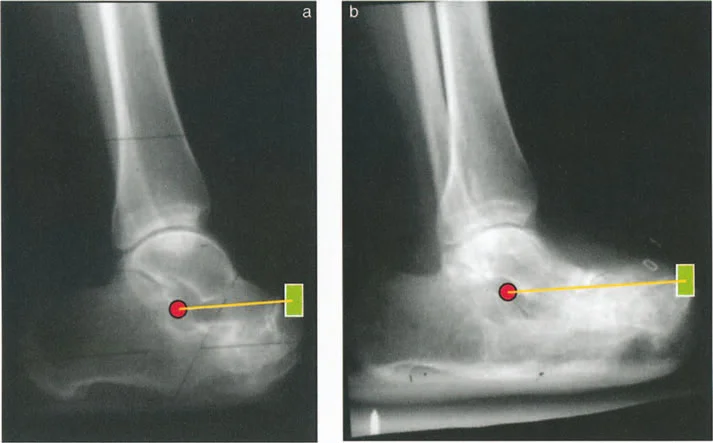

التصوير الطبي

تُعد الأشعة السينية والتصوير المقطعي المحوسب والرنين المغناطيسي أدوات حاسمة لتحديد التشوهات الهيكلية وتقييم المحاور الميكانيكية.

- الأشعة السينية (X-rays):

- الأشعة الثابتة: تُستخدم لتقييم التشوهات العظمية الواضحة، والتئام الكسور، وحالة المفاصل.

- الأشعة مع تحمل الوزن (Weight-bearing X-rays): تُظهر كيف تتصرف المفاصل والعظام تحت الضغط الطبيعي للجسم، وهو أمر حيوي لتقييم التشوهات الديناميكية.

- أشعة الأطراف الطويلة (Long Leg Films): تُؤخذ هذه الأشعة من الورك إلى الكاحل في صورة واحدة لتقييم المحور الميكانيكي الكامل للطرف السفلي وتحديد أي انحرافات.

- التصوير المقطعي المحوسب (CT Scans): يوفر صورًا ثلاثية الأبعاد للعظام، وهو مفيد بشكل خاص لتقييم التشوهات الالتوائية (مثل الورم الفخذي المفرط) وتحديد موقع مركز دوران الانحراف (CORA) بدقة.